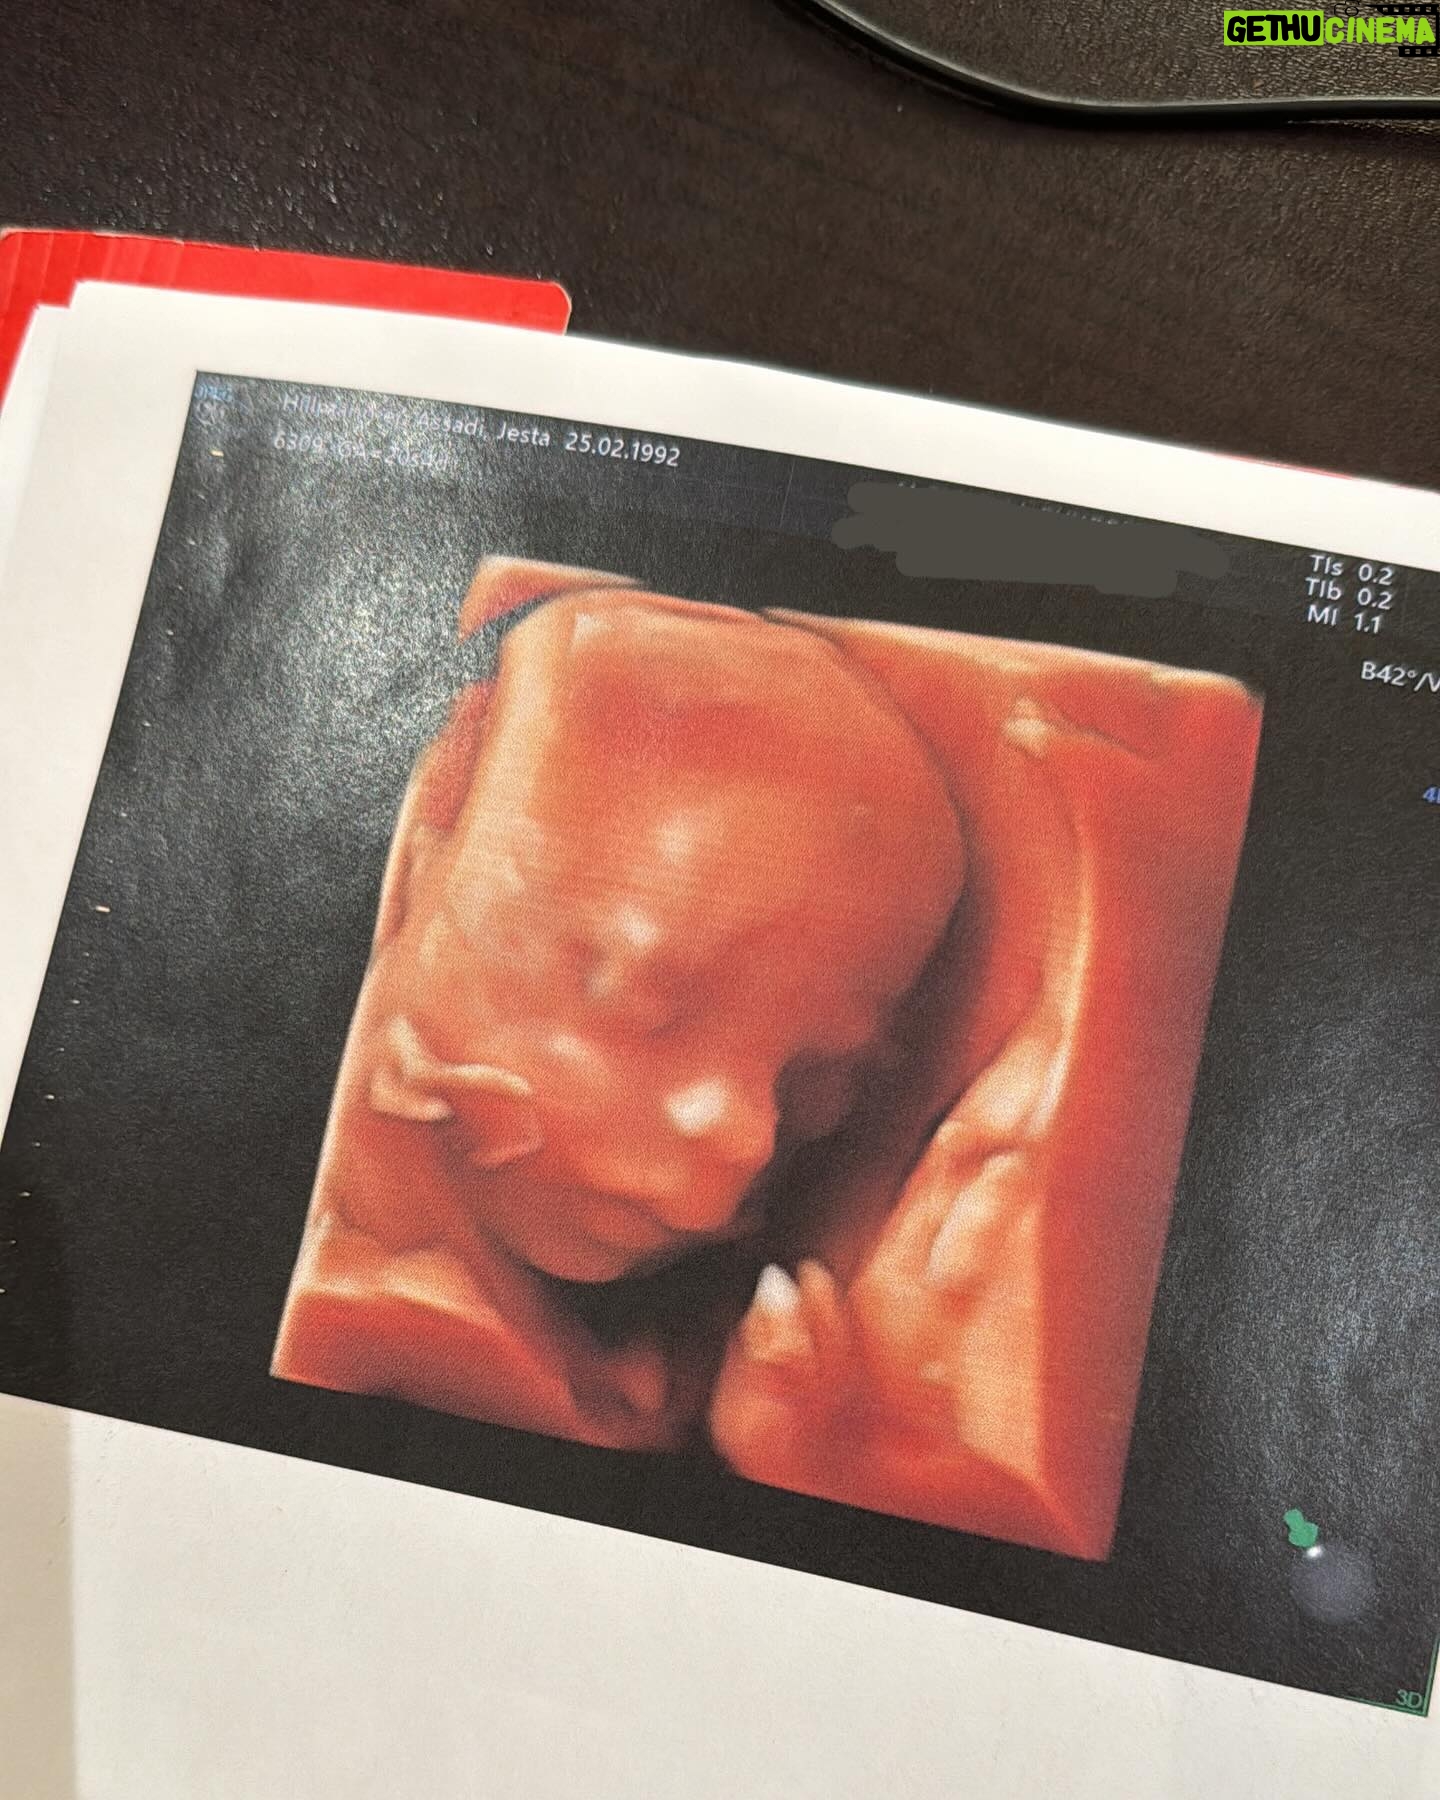

132.7K Likes – Jesta Hillmann Instagram

Caption : T2 morphologie et je dois vous annoncer QUE TOUT VA BIEN 🥹🤍 Il n’y a plus d’hématomes et bébé va super bien, il grandit parfaitement et se développe à merveille 🙏🏼Likes : 132683

132.7K Likes – Jesta Hillmann Instagram

Caption : T2 morphologie et je dois vous annoncer QUE TOUT VA BIEN 🥹🤍 Il n’y a plus d’hématomes et bébé va super bien, il grandit parfaitement et se développe à merveille 🙏🏼Likes : 132683